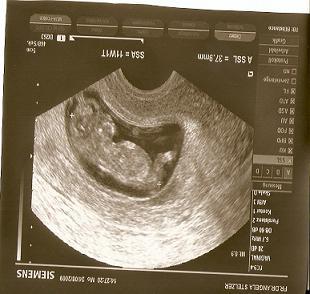

kann es ein das man in der 11 woche schon sieht wa es wird ... war heut ja beim FA und der hat ultraschall gemacht und da steht da son kleines Ding weg :D bitte helft mir muss ich die hoffnung schon aufgeben das ein mädi wird :D (da rechts hinten hängt sowas nach :D)

naja kauf e nur gelb und grün hab grad gelesen das es ankommt in welchen winkel der "gupf" da steht wenns mehr als 30 grad sind dann eher ein junge wenn weniger und paralell zur wirbelsäule dann ein mädchen :D aber ich erkenn nurnen knubbel und keine grad *gg* der FA hat nix gesagt hab sie aber auch ned gefagt ... lg

Kann mir nicht vorstellen, dass man das in der 11.SSW schon sieht! Oft ist das, was "wegsteht", auch die Nabelschnur. Aber frag doch deinen FA, der wird's am ehesten wissen!

ich bin mir sicher,das es die nabelschnur ist

Also ich finde das ist eindeutig das bein was da hoch steht und man sieht noch gar nichts was es ist naja ich muss am 11.9 wieder hin und dann bin ich 13.woche

Also ich habe gelesen, dass man es erst ab der 16 SSW sehen kann (wenn das Baby passent liegt) anderenfalls kann es noch länger dauern, deshalb mußt du dich wohl oder über gedulden. Auf dem US-Bild kann man meiner Meinung nicht annähernd ein Geschlechtsteil sehen weil das Bein davor ist und das daneben ist die Nabelschnur!!!

und es bleibt auch bei einem jungen,jetzt schon von 3 ärzten bestätigt! also das ist verschieden wann und ob man das geschlecht erkennen kann,meist liegen die kleinen auch nicht günstig. schau mal hier hab ich ein bild (beweisfoto) wo man die nabelschnur und den schniepel gut unterscheiden kann.Auch meiner freundin wurde in der 11 ssw bestätigt das sie einen jungen bekommt und dem war auch so... lg janet